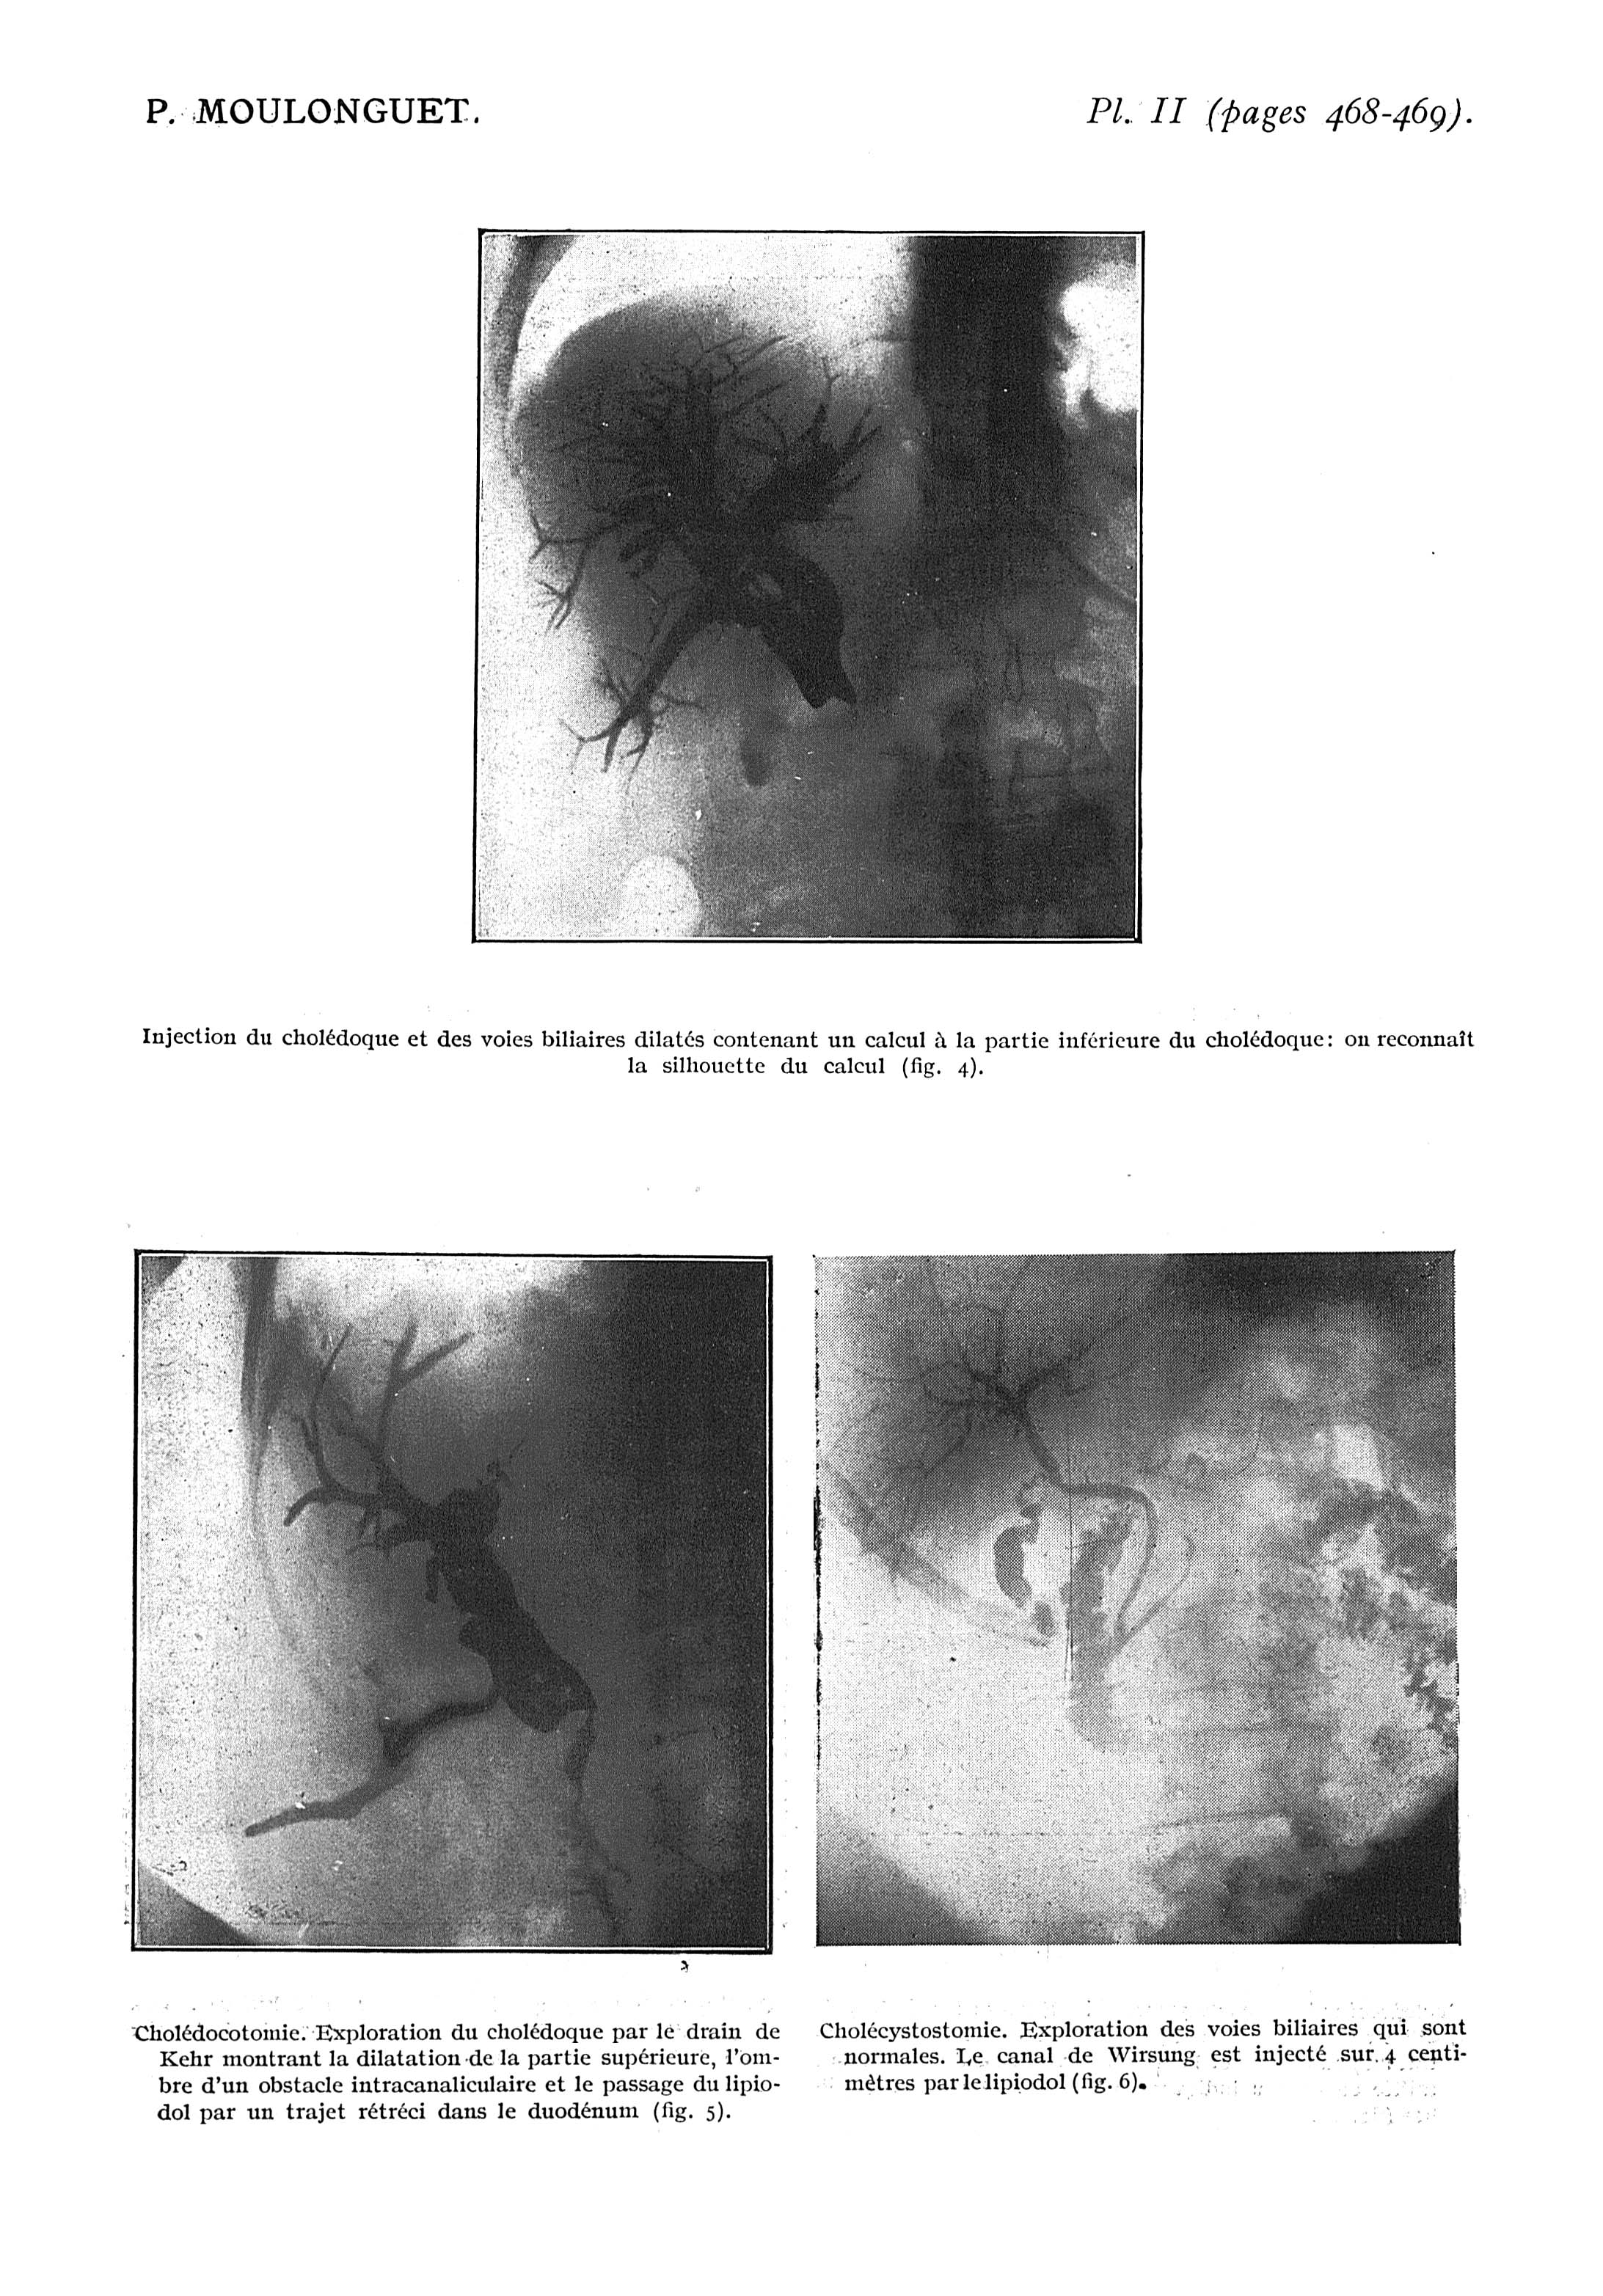

Fig. 4. - Injection du cholédoque et des voies biliaires dilatés contenant un calcul à la partie inférieure du cholédoque : on reconnaît la silhouette du calcul / Fig. 5. - Cholédocotomie. Exploration du cholédoque par le drain de Kehr montrant la dilatation de la partie supérieure, l'ombre d'un obstacle intracanaliculaire et le passage du lipiodol par un trajet rétréci dans le duodénum / Fig. 6. - Cholécystostomie. Exploration des voies biliaires qui sont normales - Paris médical : la semaine du clinicien